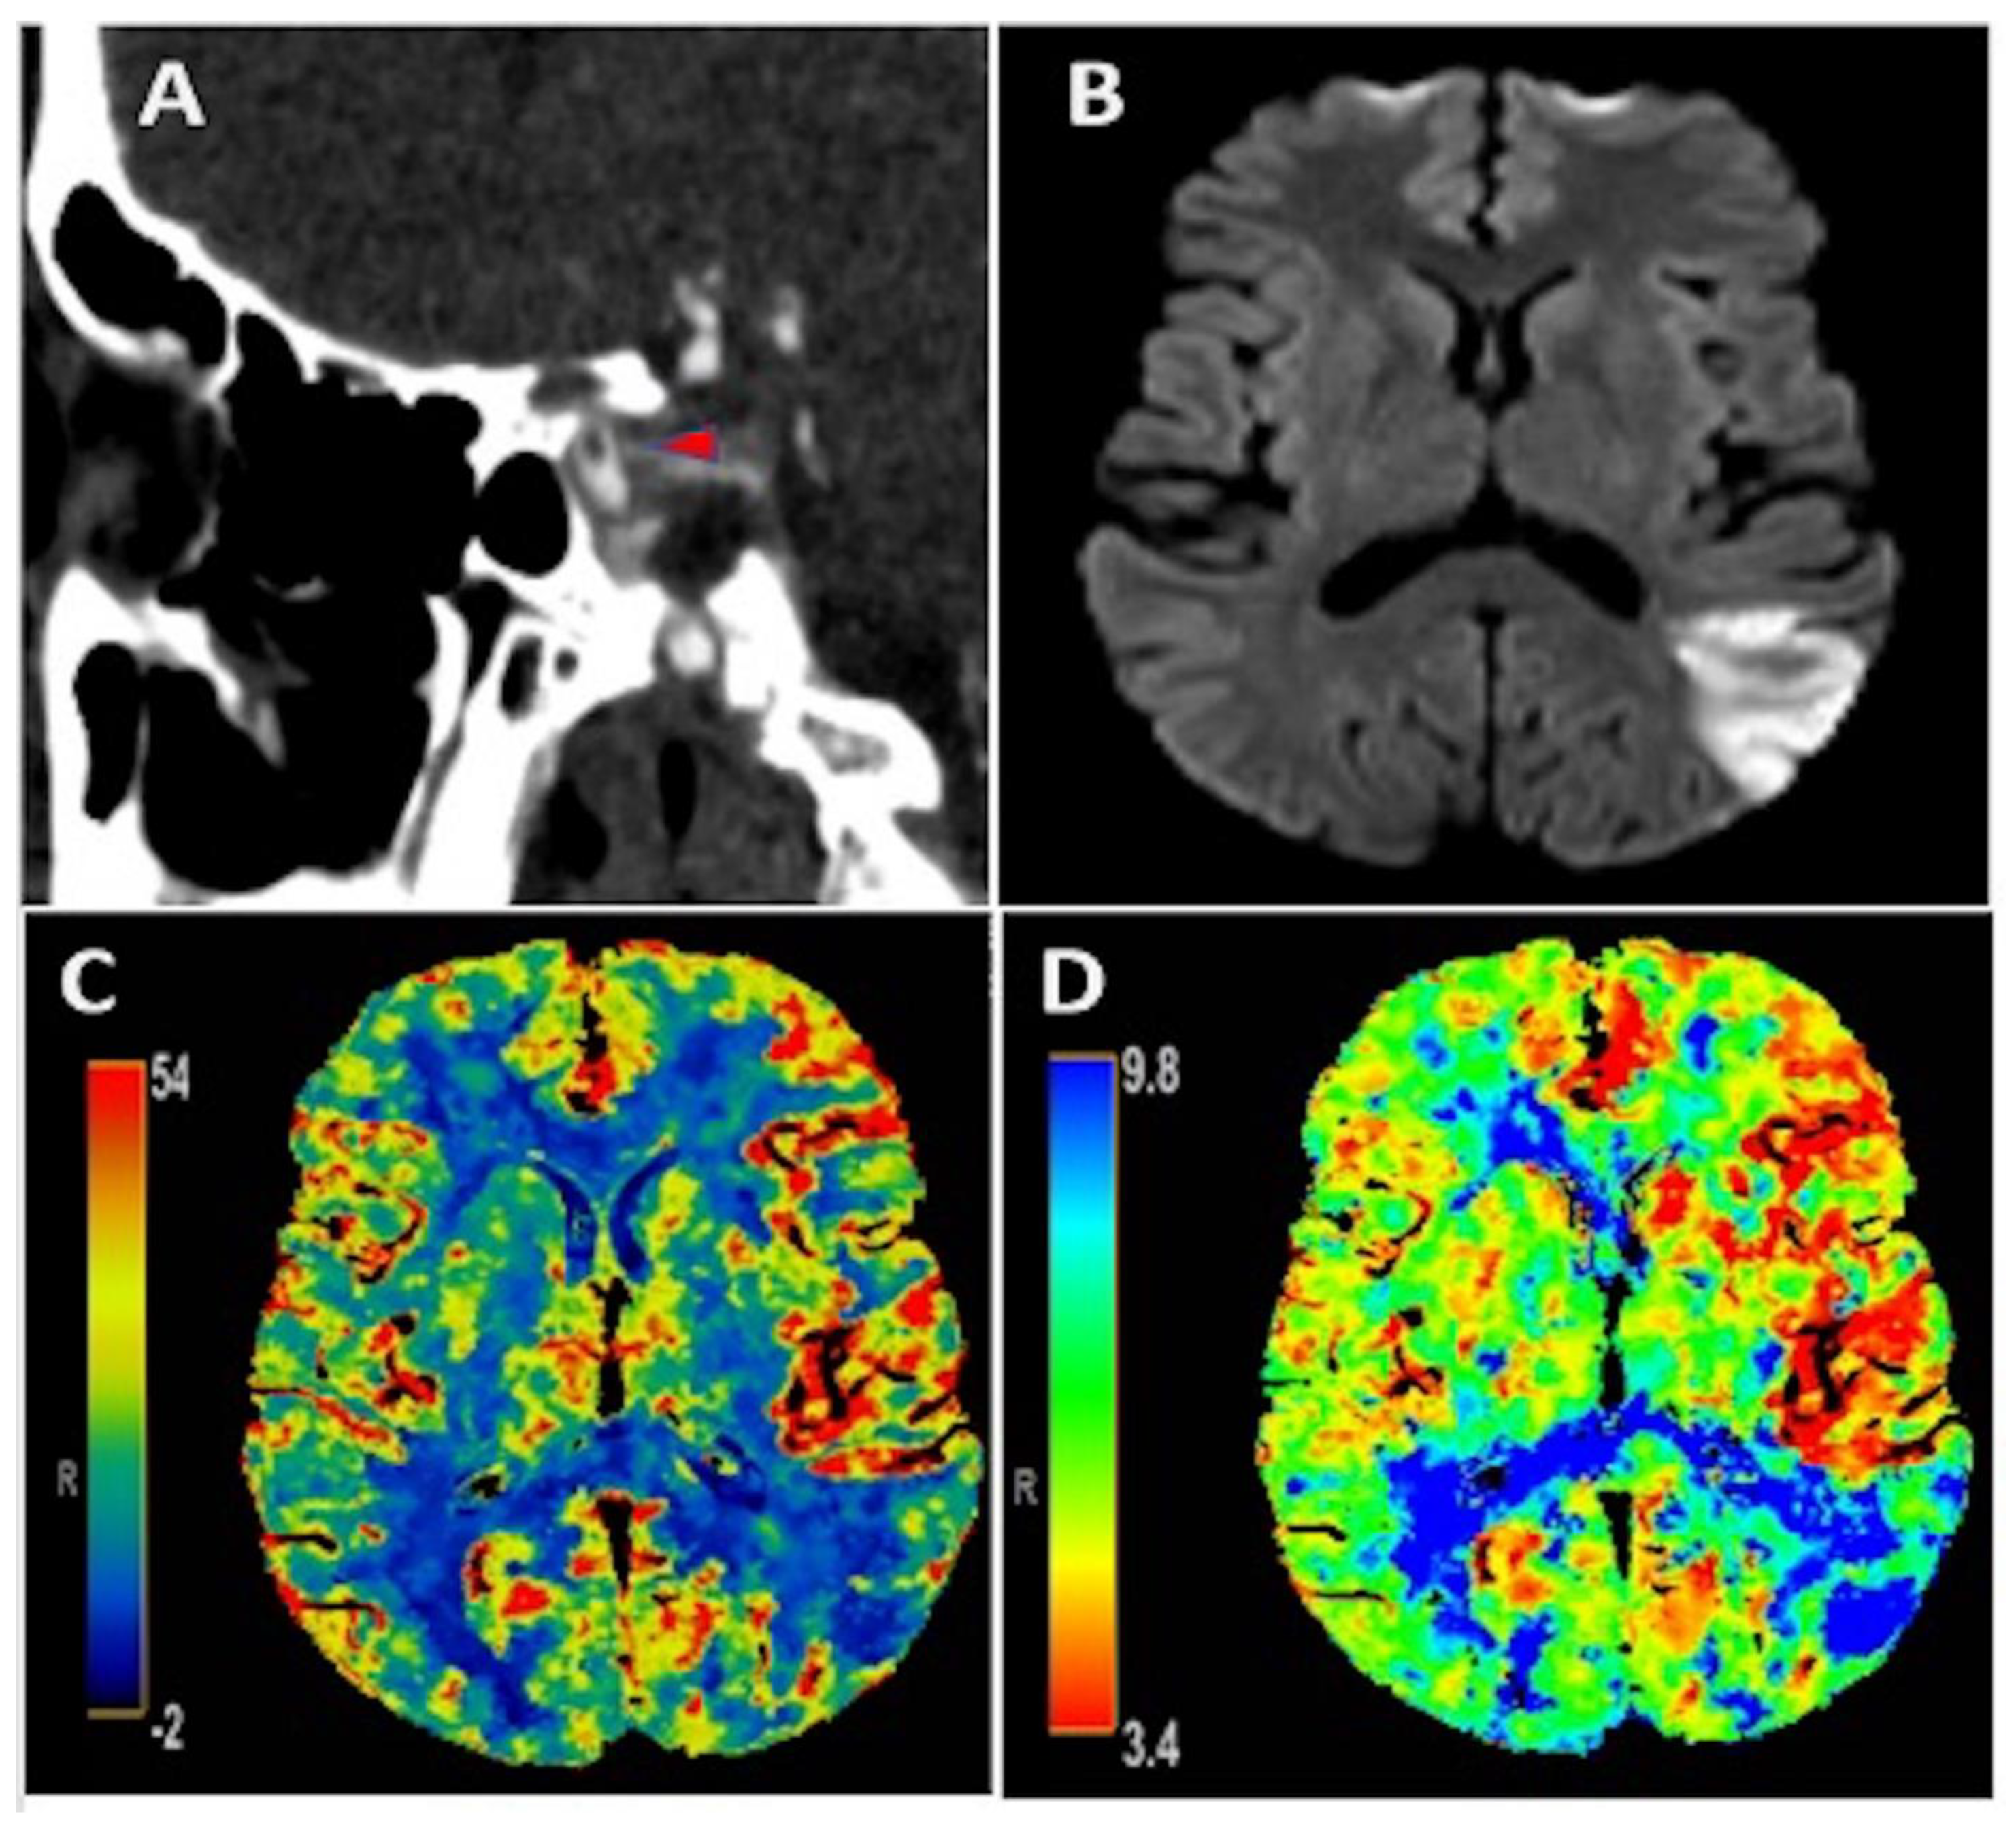

An early 50-year-old male with type 2 diabetes mellitus and hyperlipidemia presented with isolated transcortical sensory aphasia that correlated with a National Institute of Health Stroke Scale (NIHSS) of 3. CT angiography showed a free-floating intraluminal thrombus in the clinoid segment of the left internal carotid artery (Figure 1A). There was subtle hypervascularity of the anterior left middle cerebral artery (MCA) territory with an increase in regional cerebral blood flow (CBF) (Figure 1C) and cerebral blood volume (CBV), as well as decreased Tmax (Figure 1D) on perfusion imaging, consistent with hyperperfusion. Additionally, there was an area of decreased CBF and increased Tmax in the posterior left MCA territory, consistent with core infarction, which correlated to ischemic infarct area seen on MRI brain diffusion weighted imaging (Figure 1B). He did not receive acute reperfusion therapy due to presentation beyond the therapeutic window, as well as absence of favorable perfusion characteristics on initial imaging. Additionally, he was found to have an acute inferior-wall ST-elevation MI with initial troponin of 4.97 ng/mL that peaked at 10.79 ng/mL. Cardiac catheterization was deferred given the risk of hemorrhagic transformation of AIS with high doses of anticoagulation and dual anti-platelet therapy that would be needed. No contributive cardiac pathology was found on transthoracic echocardiography, cardiac CT with contrast, or on telemetry that was continued throughout admission. As an outpatient post hospital discharge, the patient had Holter monitoring that recorded about 117 hours of data and did not show any evidence of atrial fibrillation. Hypercoagulable work-up was completed both as an inpatient and also one month after hospital discharge and was unrevealing. The patient reported a recent COVID-19 exposure and clinical symptoms of chills in the days preceding this presentation, with pulmonary imaging showing peripheral ground-glass opacities in a pattern consistent with COVID-19 pneumonia. Swab-based PCR testing for COVID-19 was negative, but the IgG antibody test returned positive, suggesting recent infection. D-dimer was elevated at 1218 ng/mL on admission. He was initially treated with therapeutic anticoagulation with intravenous (IV) heparin; however this was discontinued 36 hours later due to petechial hemorrhage, as seen on repeat head imaging. He was subsequently treated with antiplatelet monotherapy. Magnetic resonance imaging (MRI) of the brain confirmed an AIS involving the left MCA territory (Figure 1B). He had an uncomplicated hospital course and was discharged in good condition with NIHSS of 2 for a mild aphasia. CT angiography of the neck was repeated one month after hospital discharge and showed resolution of ILT.

Figure 1.

Panel (A): CT angiography showing an intraluminal free-floating thrombus (red arrowhead) in the clinoid portion of the left internal carotid artery; Panel (B): MRI brain diffusion weighted imaging illustrating an acute ischemic stroke in the posterior left middle cerebral artery (MCA) territory. Panels (C,D): CT perfusion depicting increased CBF and decreased Tmax, respectively, in the anterior left MCA territory consistent with hyperperfusion in this area as well as decreased CBF and increased Tmax in the posterior left MCA territory consistent with core infarction and corresponding with ischemic stroke seen on MRI brain in Panel (B).